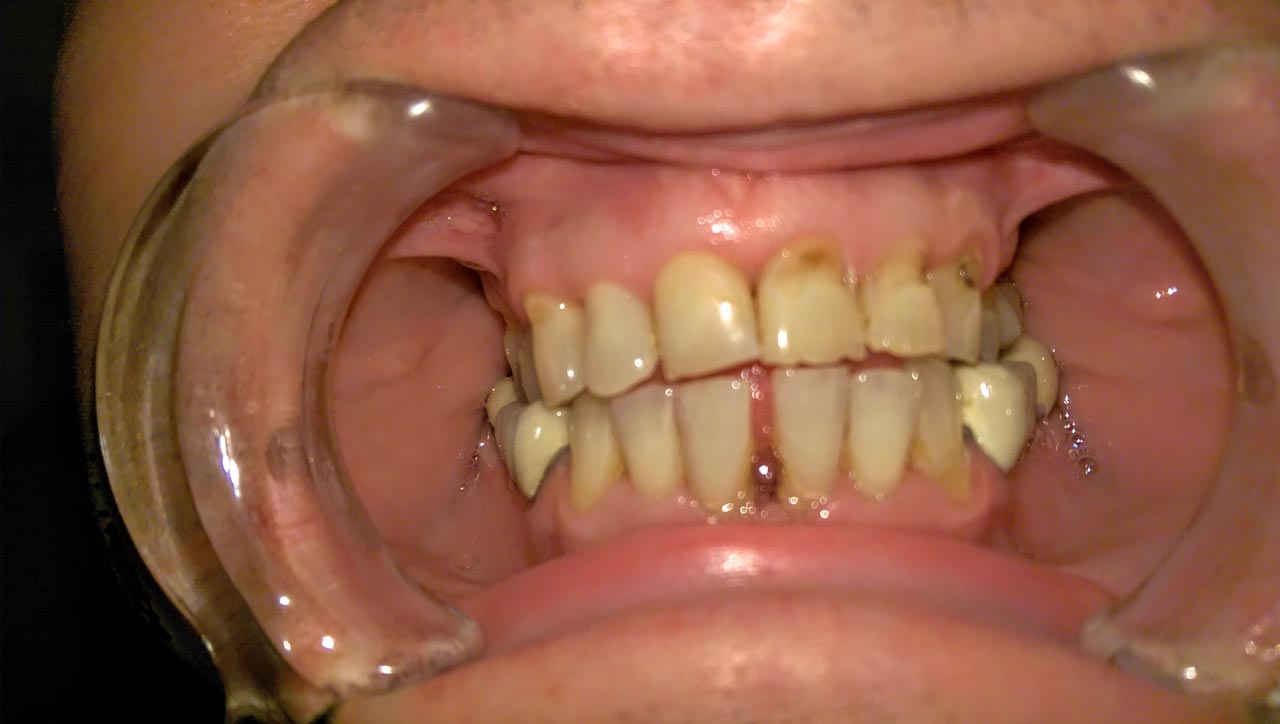

Teljes szájüregi rehabilitáció két lépésben

Ismét egy teljes szájüregi rehabilitáció két lépésben. Először az alsó fogak lettek kihúzva és azonnal implantálva, híddal ellátva, majd később a felső. IHDE svájci azonnal terhelhető implantátumok és cirkónium hidak. Dr. Kelemen Péter és a Symbion Fogtechnika közös munkája.